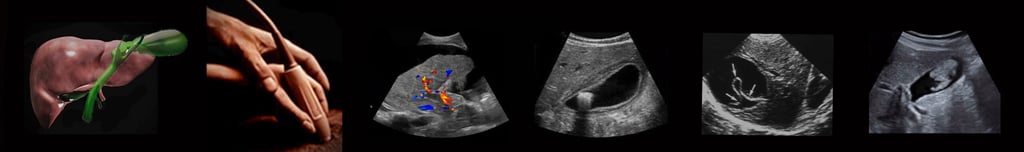

Hands-On Abdominal Ultrasound Imaging & Doppler

A Three Day Guided Experience

Learn to acquire, analyze, and trust abdominal ultrasound findings through live scanning, direct faculty guidance, and structured repetition—exactly as ultrasound is used at the bedside.

Nothing is assumed. Every image is explained. Doppler is introduced as a natural extension of anatomy and physiology, not an advanced add-on.

Ultrasound skill is built through guided experience, not passive observation. Instruction centers on live scanning, immediate feedback, and repeated practice—so technique, interpretation, and clinical reasoning develop together.